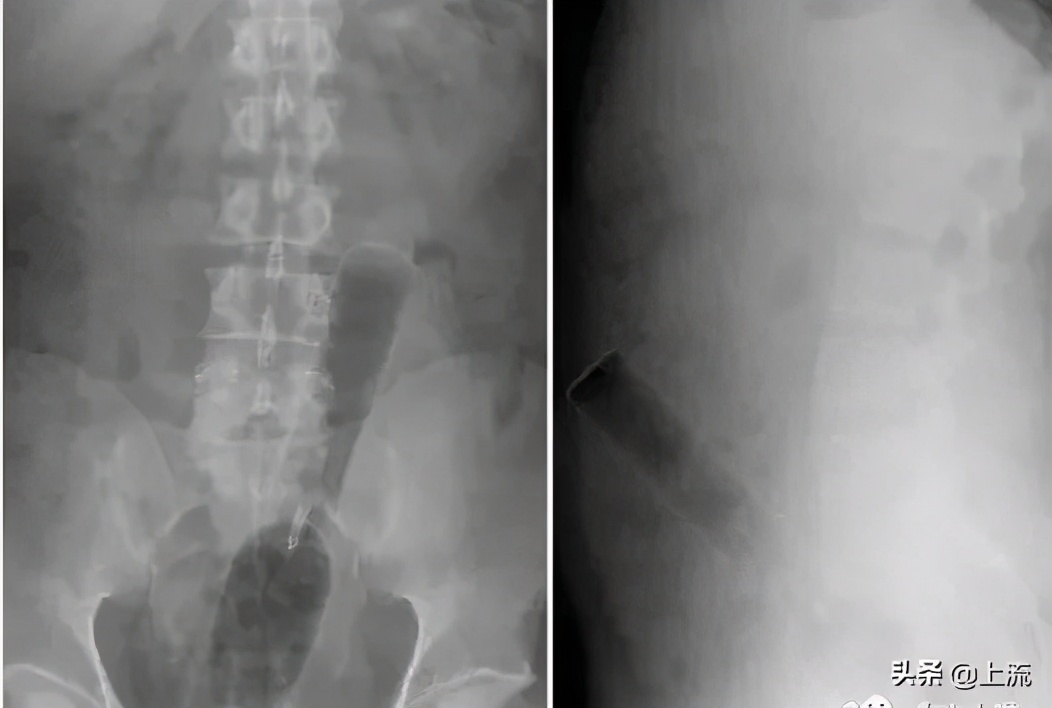

而面对这种直肠内有手机的优秀X光片,医生大概只能猜测,该病人可能是想测试这部诺基亚经典款卓越的超长待机、超频震动以及超强防水功能……对不起,编不下去了。

鉴于以上的人类迷惑行为,一名肛肠科医生见过了如此精彩纷呈的人体异物后,再看到什么都会见怪不怪了,于是这就考验着医生的另一项专业能力——编剧能力——如何能在不让病人家属知道真相的同时解释清楚这神奇的X光片。

△来源:医学手札